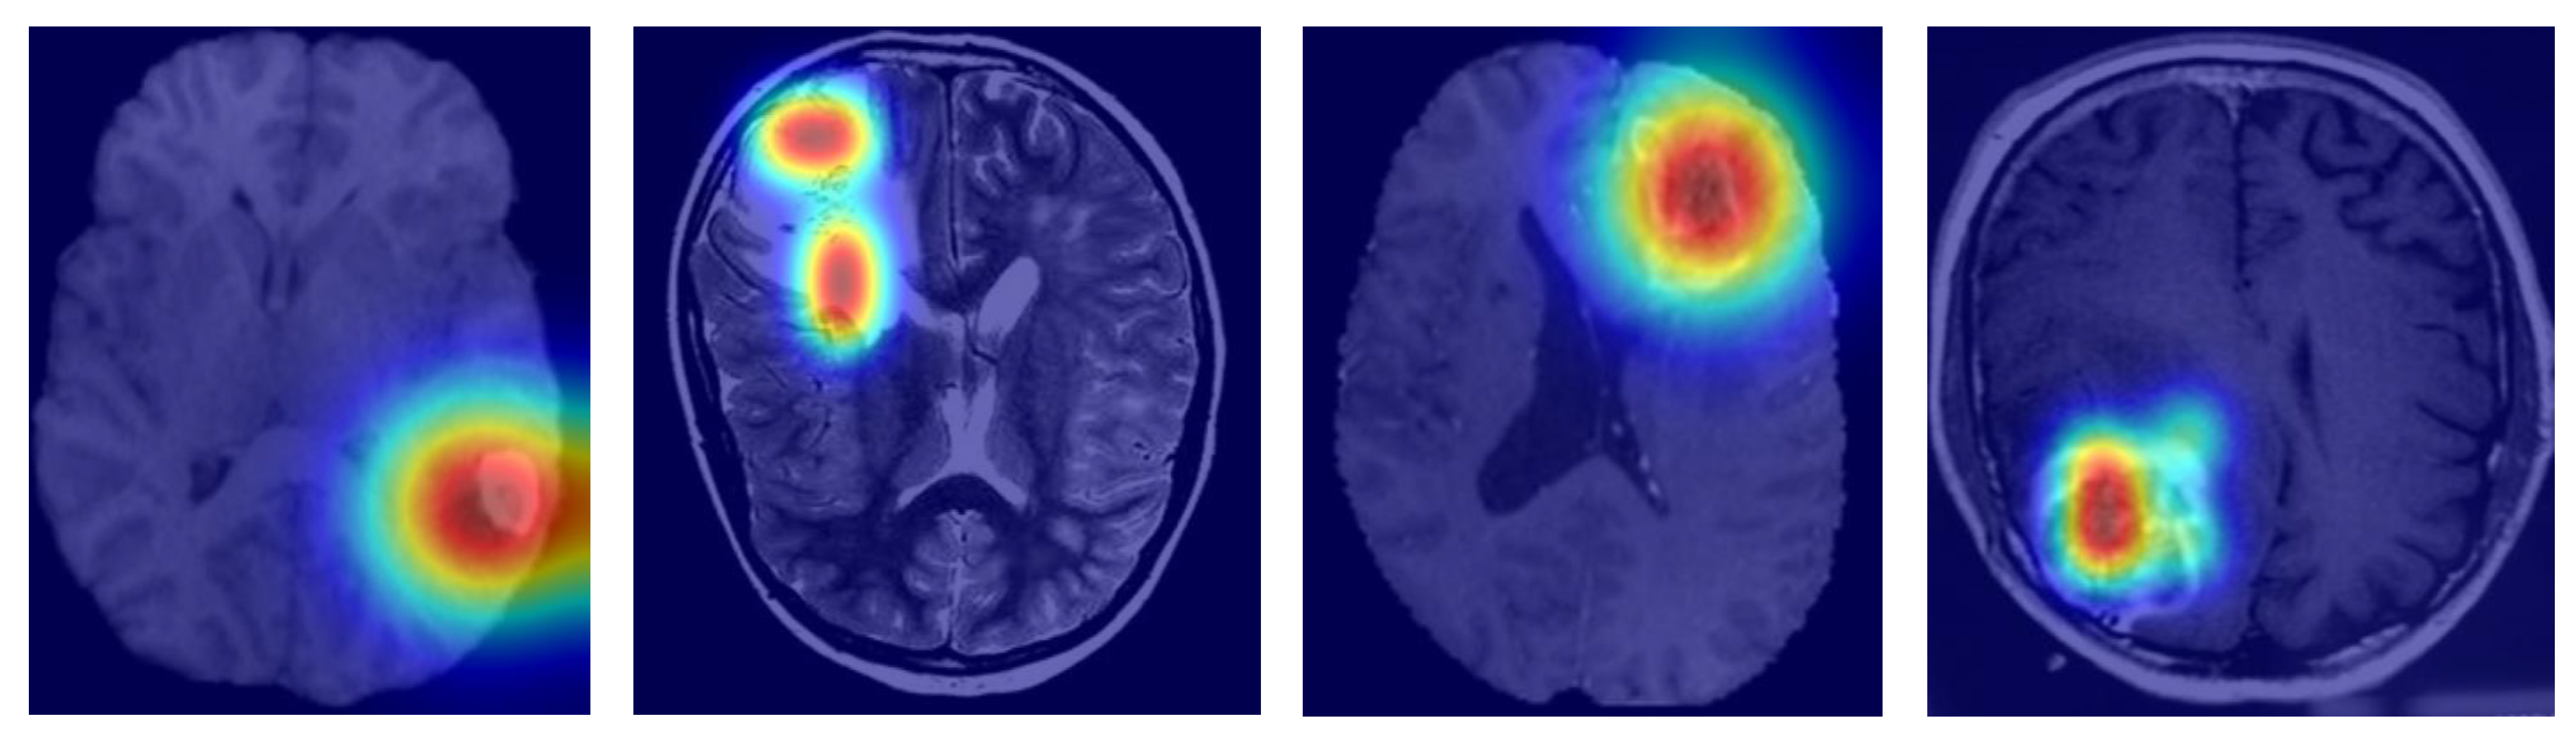

To evaluate generalization, MGMT-Net was tested on a holdout dataset of 200 cases from UCSF, NYU, and UTSW that were not used during training or validation. Despite variation in scanner type, spatial resolution, and acquisition protocol, the model demonstrated consistently strong performance across all sites and imaging conditions. With only a 2% decrease in Dice scores compared to previously reported results, MGMT-Net maintained high classification performance, achieving AUCs above 0.91 for IDH, 0.88 for 1p/19q, and 0.86 for TERT. This performance stability reinforces the robustness of the proposed model and its capacity to generalize across diverse clinical domains and data sources. This generalization is primarily attributed to the descriptive power of global structural patterns captured by the Transformer branch in the latter stages of the encoder, which helps mitigate inter-institutional variability—a well-documented challenge in multi-center neuroimaging datasets. Additionally, the CMAF module enhances adaptability to modality inconsistencies by assigning soft attention weights that dynamically adjust the influence of each MRI sequence at the voxel level Figure 4.

To systematically evaluate each major architectural component, we conducted a series of ablation studies in which specific modules were selectively disabled to isolate their contributions. Replacing the CMAF module with a naïve concatenation of modalities (NCAM) led to a decrease of approximately 2.3 to 3.7 points in segmentation Dice scores and a 1.5 to 2.2-point reduction in AUC for molecular marker prediction. Substituting the Swin Transformer branch with a deeper CNN significantly degraded biomarker classification performance—dropping the AUC for IDH prediction from 0.94 to 0.91 and TERT prediction from 0.90 to 0.87. Furthermore, replacing attention-based pooling with global average pooling resulted in a 2–4% decline in classification accuracy, particularly for tumors with high spatial and morphological heterogeneity. These ablation results underscore the synergistic effect of MGMT-Net’s multi-modal attention fusion, hybrid Transformer–CNN encoding, and task-specific decoder heads in achieving robust performance on both segmentation and molecular classification tasks. The findings validate the effectiveness of the model’s integrative architectural design Figure 5.

Likewise, for molecular marker classification, MGMT-Net demonstrated strong generalization in the external test cohort, achieving AUC values of 0.91 (IDH), 0.88 (1p/19q), and 0.86 (TERT)—closely matching internal benchmarks of 0.94, 0.91, and 0.90, respectively. These results indicate that MGMT-Net maintains predictive accuracy across spatial representations, independent of training-time conditions, which is critical for use in multi-center clinical trials. The model architectural robustness can be attributed to two key components. First, the CMAF module enables adaptive weighting of MRI sequences based on their local quality and relevance. For example, in external datasets with noisy FLAIR images, higher attention weights were allocated to T2 or T1ce sequences, compensating for unreliable input. Second, the hybrid Transformer–CNN encoder captures global inter-scanner anatomical patterns, thereby reducing sensitivity to scanner-specific voxel intensity variations—a common issue in multi-center neuroimaging. This is further supported by segmentation overlays and attention map visualizations from the external dataset, which reveal anatomically aligned activation regions. These findings suggest that the model learns robust, generalizable representations rather than overfitting to scanner-specific or protocol-specific patterns. These results validate MGMT-Net’s applicability to domain generalization and real-world clinical use without requiring site-specific retraining. This level of reliability addresses a persistent challenge in medical AI: the tendency of models trained on limited, curated datasets to underperform in diverse clinical environments.

To gauge interpretability, we came up with Grad-CAM visualizations and attention heatmaps for typical cases stemming from biomarkers. As depicted in Figure 6, MGMT-Net kept on highlighting the tumor regions, which were of utmost biological relevance, during its prediction. In the case of IDH mutation, the most activated areas were around the non-enhancing tumor core; whereas for TERT prediction, the attention was at the enhancing rim and the necrotic boundary; and for 1p/19q co-deletion, the model was focused on the diffuse infiltrative margins seen in the FLAIR sequences.

The noted patterns correspond greatly with the radiogenomic associations that have been mentioned in previous studies and hence, they are an indication of the biological plausibility of MGMT-Net’s predictions. Furthermore, by looking at the CMAF weights, we found modality-specific attribution: FLAIR features were the most prominent in the peritumoral edema delineation, T1ce showed the vascular regions, and T2 was for the boundary sensitivity. Such findings, combined, lead to the conclusion that MGMT-Net is not only a predictor of accurate outcomes but also a provider of the interpretable cues that are consistent with neuro-oncological knowledge.